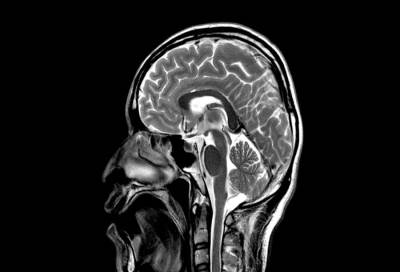

قال علماء اميركيون ان الدماغ الحي مجبول على حب المواد الحلوة، لانها غنية بالسعرات الحرارية اللازمة لديمومة الجسم الحي وديمومته بقائه على الارض خصوصا اوقات المجاعات.

وقال الباحث الذي اجرى تجاربه على فئران المختبرات ان حب الانسان والحيوانات للحلويات تطور منذ القدم لاحتوائها على كميات عالية من السعرات الحرارية اللازمة لنموها.

وقال دي اروجو الذي نشر دراسته في مجلة “نيرون” لعلوم الاعصاب، ان الجسم الحي ينجذب كما يبدو نحو السكر لاحتوائه على السعرات الحرارية.